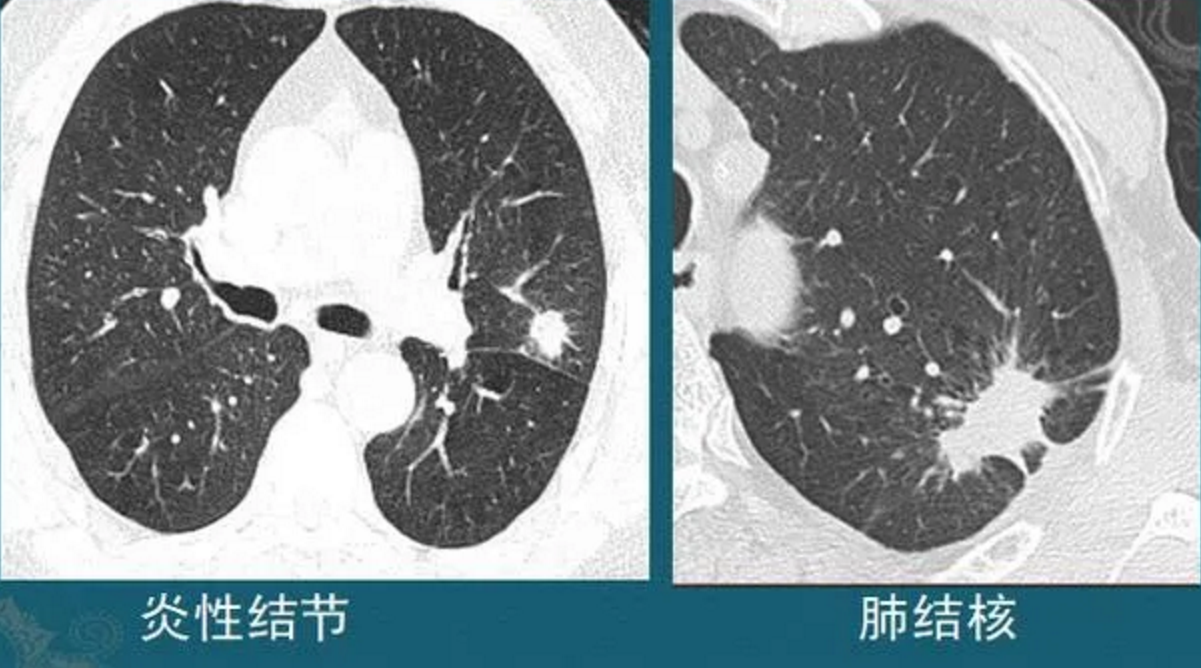

4.炎症、结核造成的结节

这种结节有时单纯从CT片的形态分析,跟肺癌鉴别困难,需要抗炎治疗后复查,或者增强CT看结节的强化特点,炎症结节常常明显均匀强化,结核球一般不强化或者环形包膜样强化(肺结核会破坏内部组织包括血管,引起广泛坏死),肺癌多为轻中度不均匀强化(肿瘤血管少而乱)。